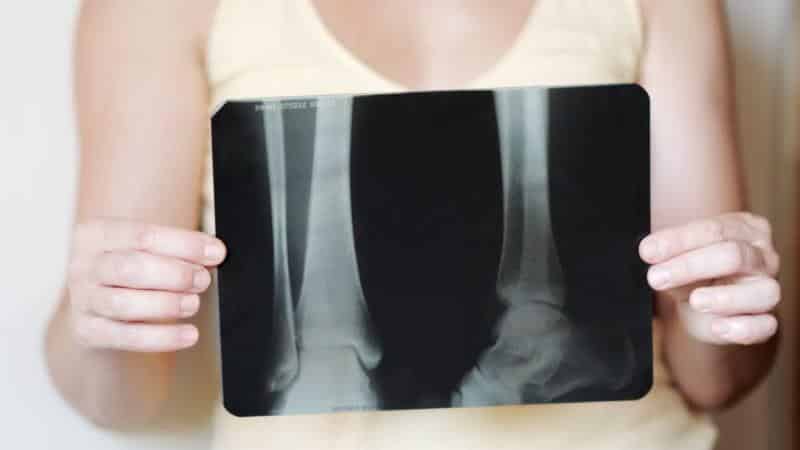

Рентгеновское исследование проводится в специально оборудованном кабинете, и для его выполнения не требуется никакой предварительной подготовки. Время, необходимое для процедуры, составляет около 10 минут.

Показания для рентгена зависят от предполагаемой патологии, что определяет методику проведения исследования:

- Травма кости. Пациента укладывают на спину на кушетку, сгибают ногу в колене, а стопу располагают перпендикулярно поверхности. Это позволяет получить прямую заднюю проекцию, на которой четко видны все три кости, формирующие сустав.

- Повреждения сустава и большеберцовой кости. Больной занимает сидячее положение, пораженная нога располагается на специальной подставке. Исследование обычно выполняется в боковой проекции, но чаще пациента укладывают на бок. При этом здоровую ногу подгибают к животу, а больную оставляют выпрямленной.

- Патологии свода стопы. Пациент встает на одну ногу, другую поджимает. В этом случае рентген голеностопного сустава выполняется в двух проекциях: прямой и боковой.

- Признаки разрыва синдесмоза. Для диагностики данной патологии делают снимок в задней проекции с ротацией стопы. Пациент лежит на спине, ноги вытянуты, а поврежденная стопа слегка поворачивается внутрь.

Особенности. Для защиты остальных органов от радиационного воздействия используются свинцовые фартуки.